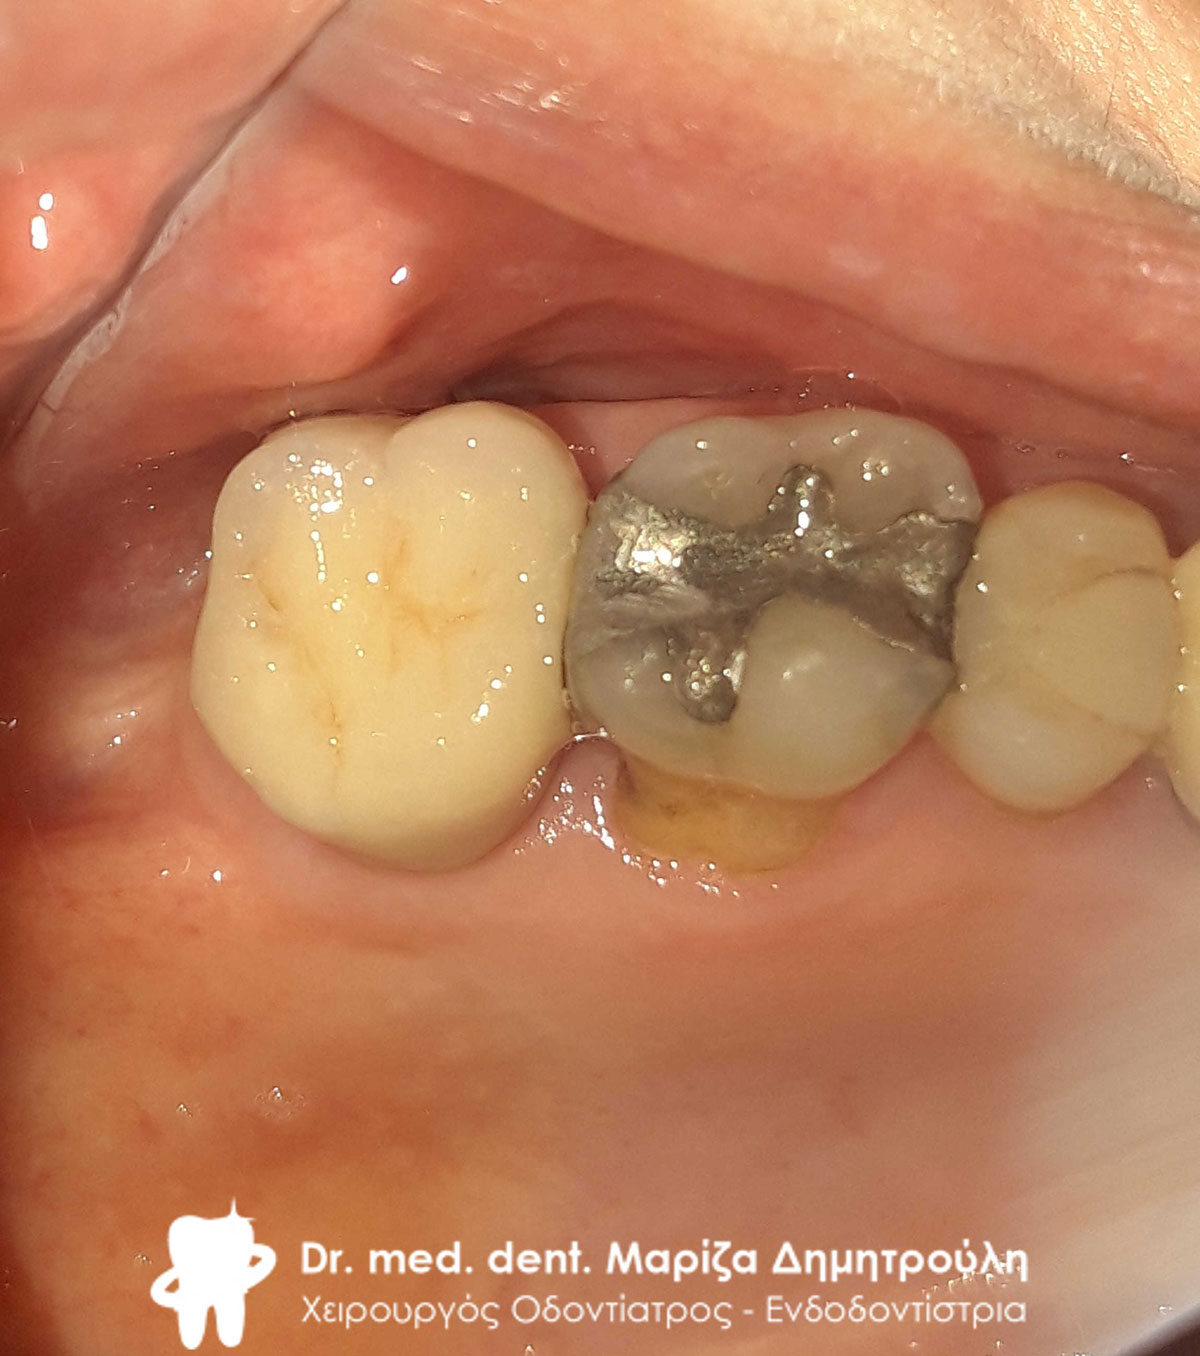

Περιστατικό – Ολοκεραμική στεφάνη / θήκη ζιρκονίου στην αριστερή πλευρά της κάτω γνάθου

Η ασθενής είχε ένα παλιό μαύρο σφράγισμα αμαλγάματος το οποίο την πονούσε. Μετά την κλινική και ακτινογραφική εξέταση του δοντιού αποφασίστηκε η αφαίρεση του παλιού σφραγίσματος, η νέα ανασύσταση και η κάλυψη του δοντιού με ολοκεραμική θήκη δοντιού, καθώς το οδοντικό έλλειμμα ήταν μεγάλο.

Αρχική κλινική εικόνα του δοντιού με το παλιό μαύρο σφράγισμα αμαλγάματος

Τελική εικόνα του δοντιού με τη νέα ολοκεραμική στεφάνη